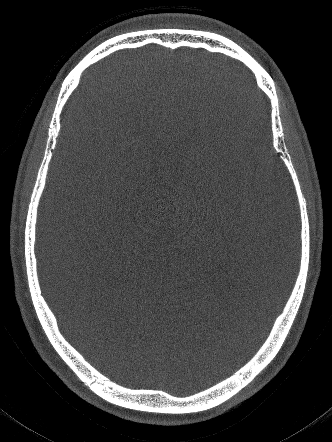

We use Adam optimization with learning rate of 0.000010.000010.00001 and select the network parameters that achieved the best RPE prediction on our validation dataset. Our network achieves an average RPE deviation from the Gt of 0.0310.0310.031 mm on the test dataset, as depicted in Fig. 1.

Figure 1: Network estimated RPE and different reconstructions, all revealing a RPE of 0.34absent0.34\approx 0.34 mm.